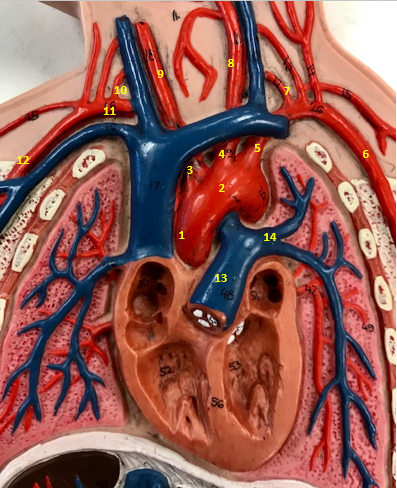

Aorta

Name #2

Brings blood out of left ventricle

Function of aorta

Brachiocephalic artery

Name #3

Supplies oxygenated blood to right arm shoulder neck and head

Function of brachiocephalic artery

Left common carotid artery

Name #4

Supplies oxygenated blood to left neck and head

Function of left common carotid artery

Left subclavian artery

Name #5

Supplies oxygenated blood to left arm shoulder

Function of left subclavian artery

Left axillery artery

Name #6

supplies blood to left armpit and upper limb

Function left axillary artery (6)

Left vertebral artery

Name #7

Supplies blood to brain and spinal cord

Function of left vertebral artery (7)

Left common carotid artery

Name #8

Supplies blood to left neck and head

Function of left common carotid artery (8)

Right common carotid artery

Name #9

Supplies oxygenated blood to right neck and head

Function of right common carotid artery (9)

Right vertebral artery

Name #10

Supplies blood to brain and spinal cord

Function of right vertebral artery (10)

Right subclavian artery

Name #11

Supplies blood to right arm and shoulder

Function of right subclavian artery

Right axillery artery

Name #12

Supplies blood to right armpit and upper limb

Function of right axillery artery (12)

Pulmonary trunk

Name #13

Bring blood out of right ventricle to lungs

Function of pulmonary trunk (13)

Left pulmonary artery

Name #14

Bring blood to left lung

Function of left pulmonary artery (14)